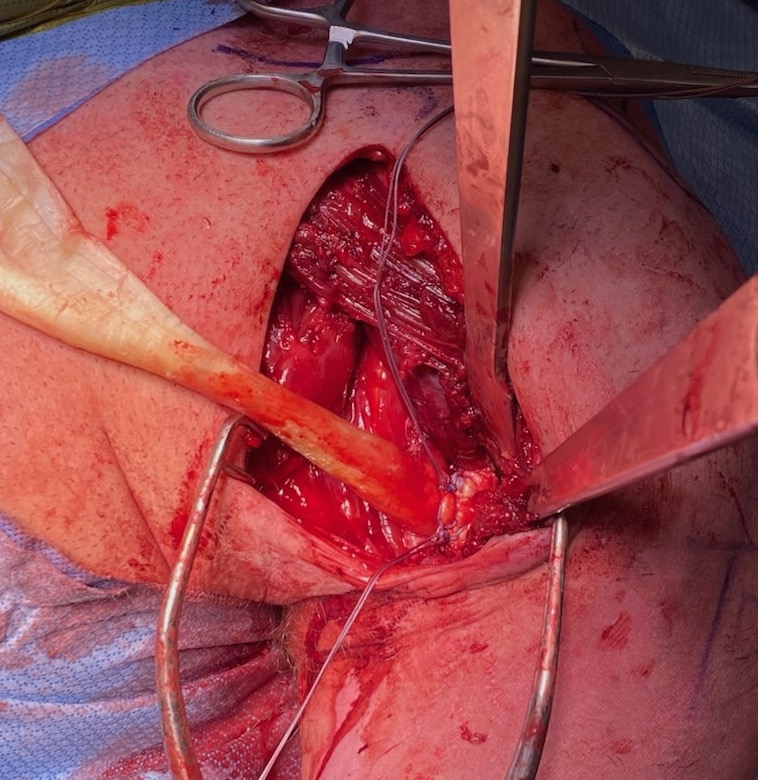

Allograft reconstruction: achilles tendon sutured anchored to humerus, and pul ve taft through muscle belly

Right shoulder: allograft has been passed through sternal and clavicular muscle bellies and is being sutured back onto itself